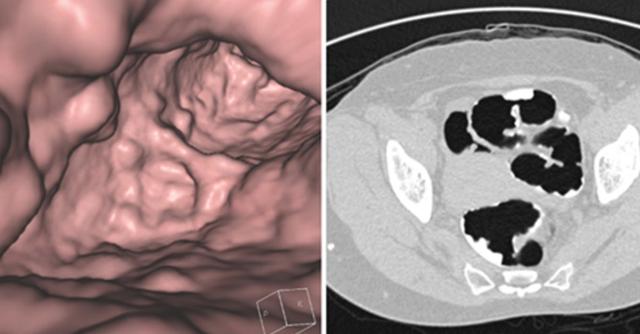

تنظير القولون الظاهري للأمعاء استعراض ووصف الإجراء الدواء 2020